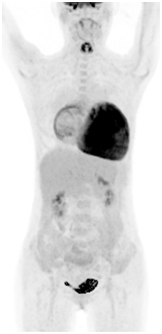

医师决定行二尖瓣机械瓣置换术(保留瓣下结构),三尖瓣成形术,房间隔缺损人造补片修补术,动脉导管未闭切段缝合术。术前为排外手术禁忌证,2022.11行PET/CT示:巨大心脏显影,房室各壁心肌代谢明显增高。

(图1)先天性心脏病患者(女,41岁)18F-FDG PET/CT显像图。1A.全身最大密度投影图示心脏明显扩大,房室各壁糖代谢明显增高;2B.心脏断层显像示各室壁糖代谢明显增高,SUVmax为11.5;1C.横断面、冠状面、矢状面三个不同层面示心腔明显增大,各室壁糖代谢明显增高。图2同一患者胸片。2A.2022年10月(手术前)胸片:心胸比为0.88;2B.2022年12月(手术后)胸片:心胸比例为0.76。